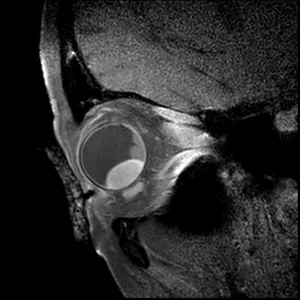

3D T1 SPIR Gd

3D T1-weighted sequence with fat supression after gadolinium contrast administration. This sequence is used to determine the enhancement pattern of the intra-ocular masses. The sequence parameters are the same as the 3D T1 SPIR sequence.

Main sequence parameters:

Scan duration

02:07 min

Sequence type

3D TSE

TR/TE

400 / 31 ms

ACQ voxelsize

0.80 x 0.80 x 0.80 mm

REC voxelsize

0.36 x 0.36 x 0.40 mm

WFS (pix) / BW (Hz)

1.78 / 244

TSE factor / shot length

20 / 188 ms

Fat saturation

SPIR

View the full sequence details.